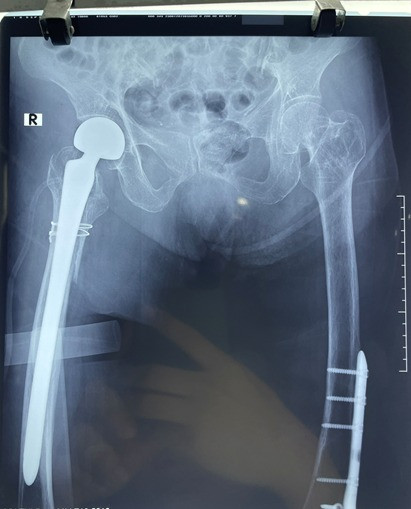

![]() |

| Hình ảnh sau phẫu thuật thay khớp háng |